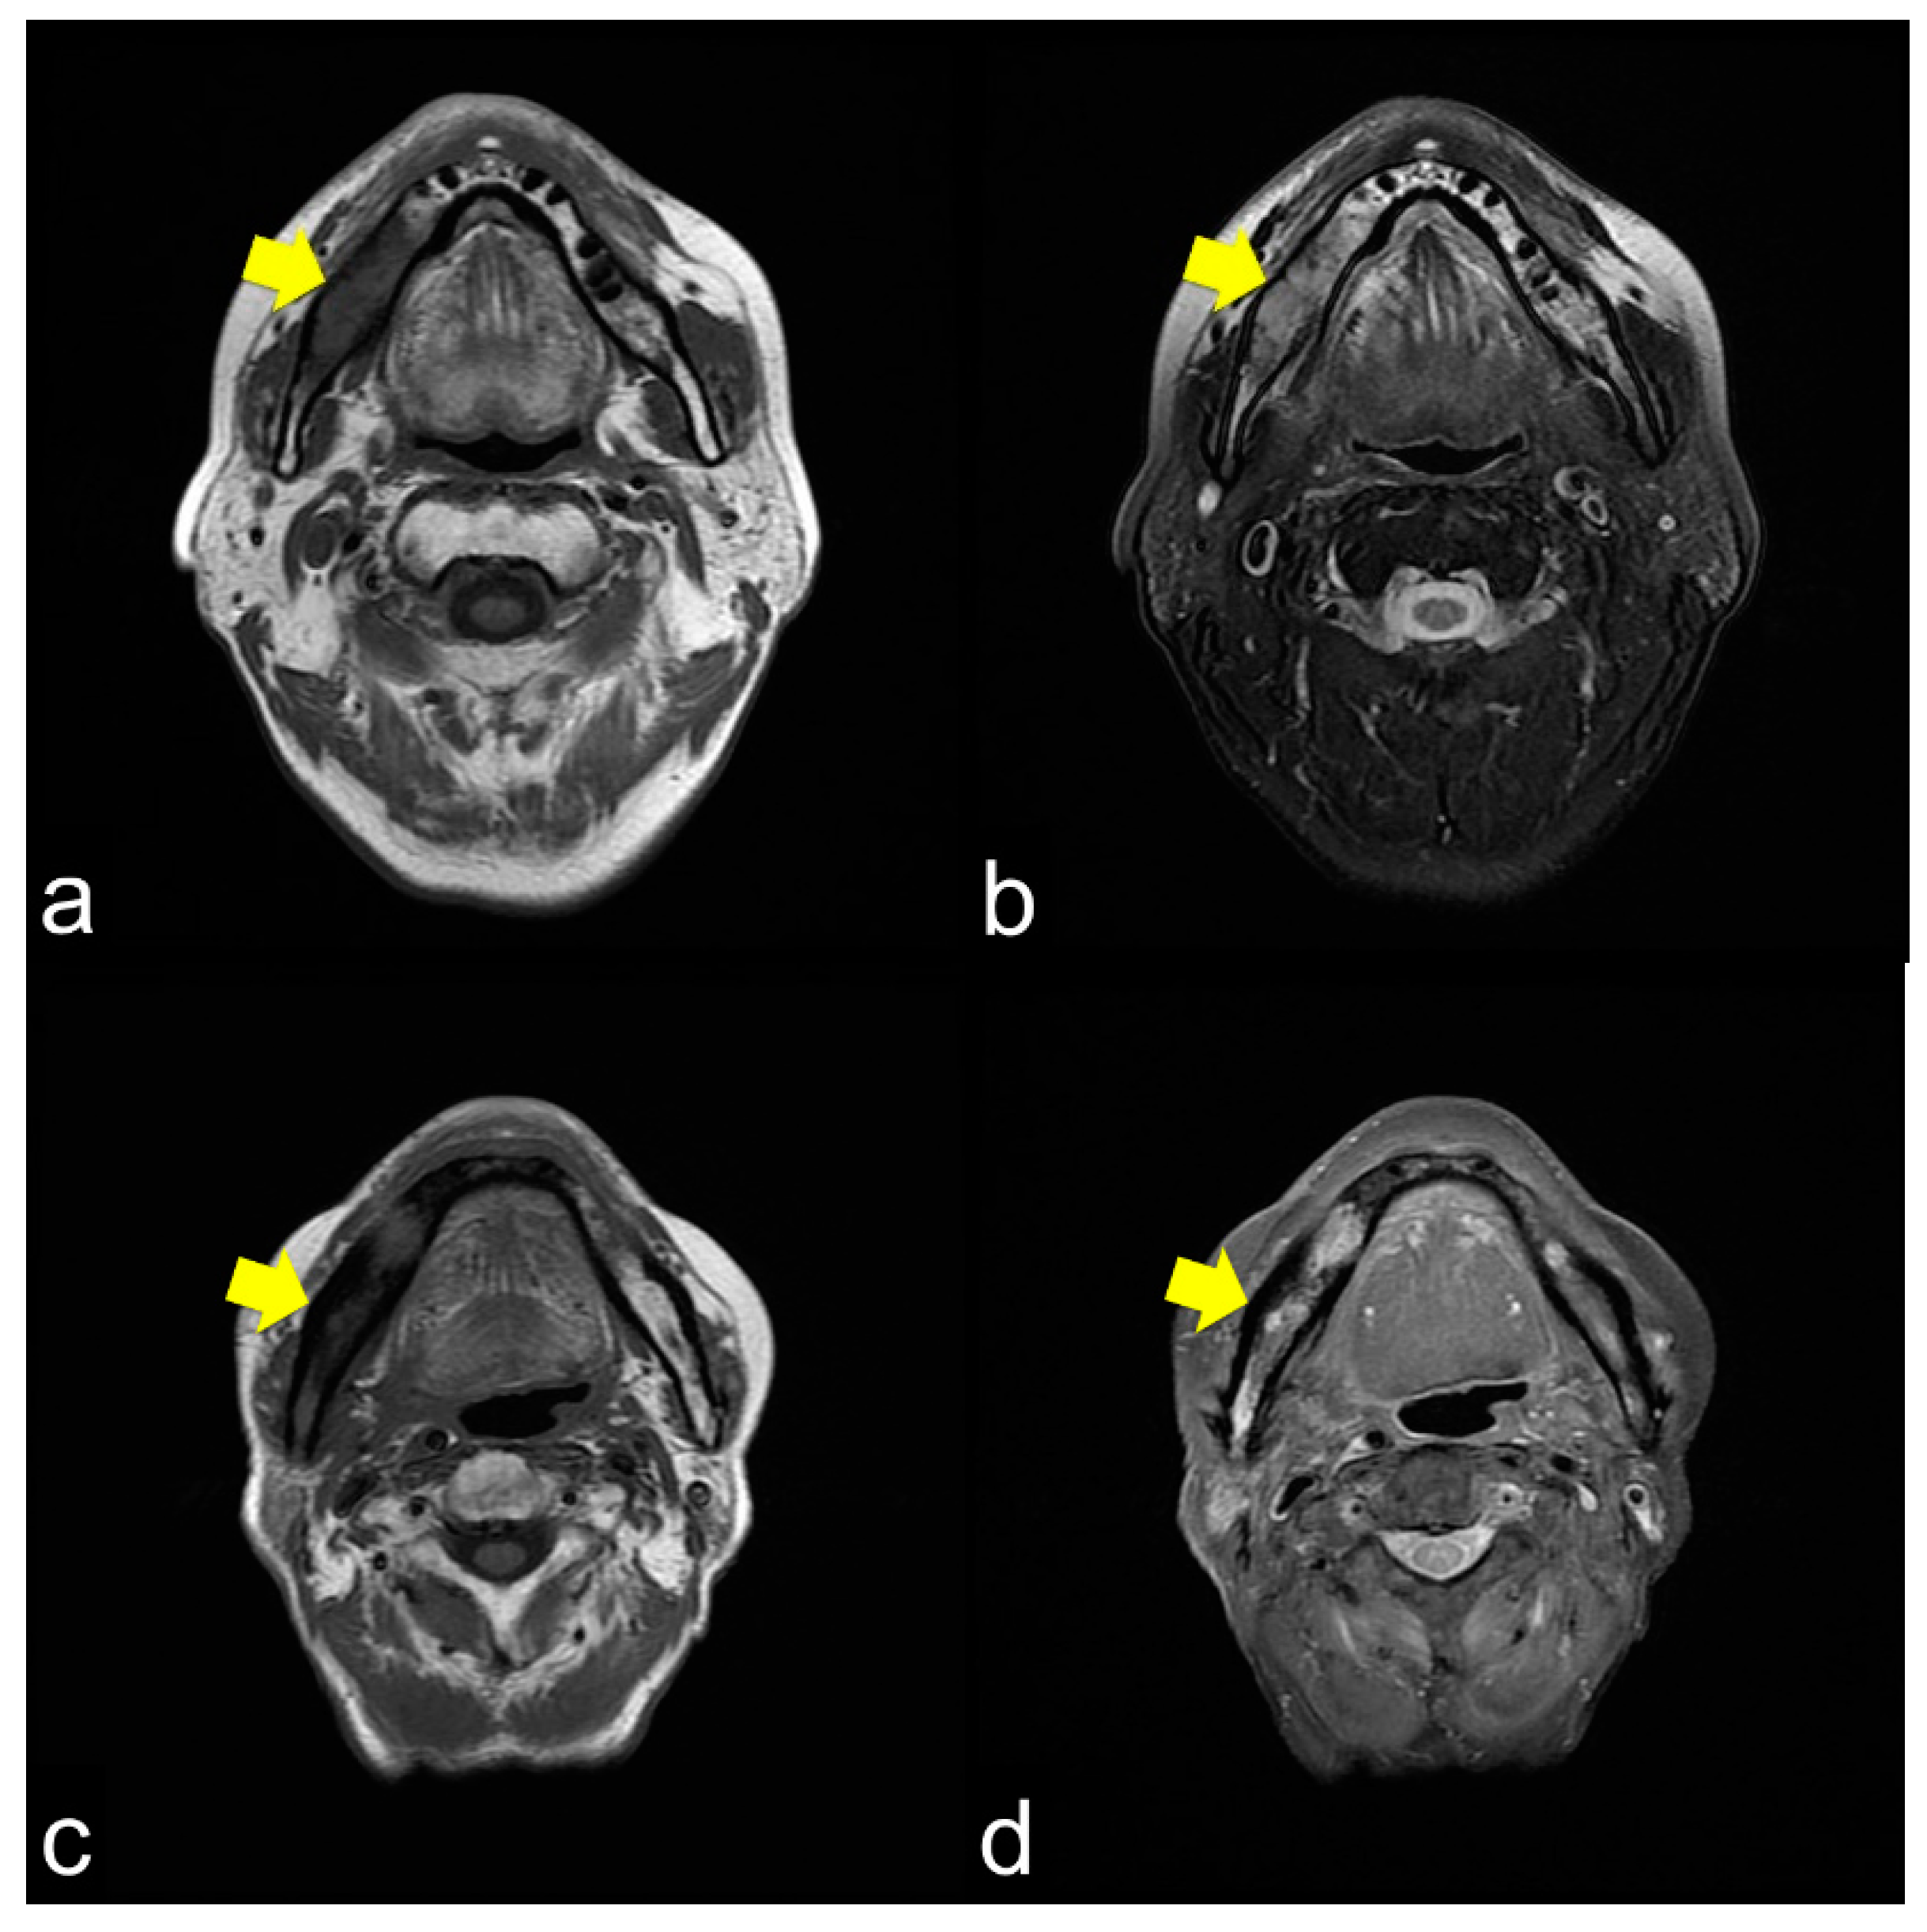

All 42 (100%) patients showed T1 WI hypo-intensity in the symptom region (Figure 2a,c,e). In contrast, the T2 WI showed various aspects. Thirty (71.4%) patients with T2 WIs showed homogeneous hyper-intensity (Figure 2b), which showed a relatively mild inflammatory condition of bone marrow clinically. Heterogeneous hyperintensity was observed in 11 (26.2%) patients (Figure 2d). One patient (2.4%) showed homogeneous hypointensity (Figure 2f).

Figure 2.

(a) Axial T1-weight image (T1 WI) shows low signal intensity from the molar lesion to the ramus on right side of the mandible (arrowhead); (b) Axial T2-weight image (T2 WI) reveals high signal intensity on the right side of the mandible (arrowhead). The margins between the normal and abnormal bone marrow are not distinct. This condition usually shows mild inflammation of the ORN; (c) Axial T1 WI shows low signal intensity from the molar lesion to the ramus on the right side of the mandible (arrowhead); (d) Axial T2 WI reveals heterogeneous intensity on the right side of the mandible (arrowhead). The margins between the normal and abnormal bone marrow are not distinct. This condition usually results in severe ORN inflammation; (e) Axial T1 WI shows low signal intensity from the molar lesion to the ramus on the right side of the mandible (arrowhead); (f) Axial T2 WI reveals low signal intensity on the right side of the mandible (arrowhead). The margins between the normal and abnormal bone marrow are not distinct. This condition is bone necrosis, which shows less inflammation.